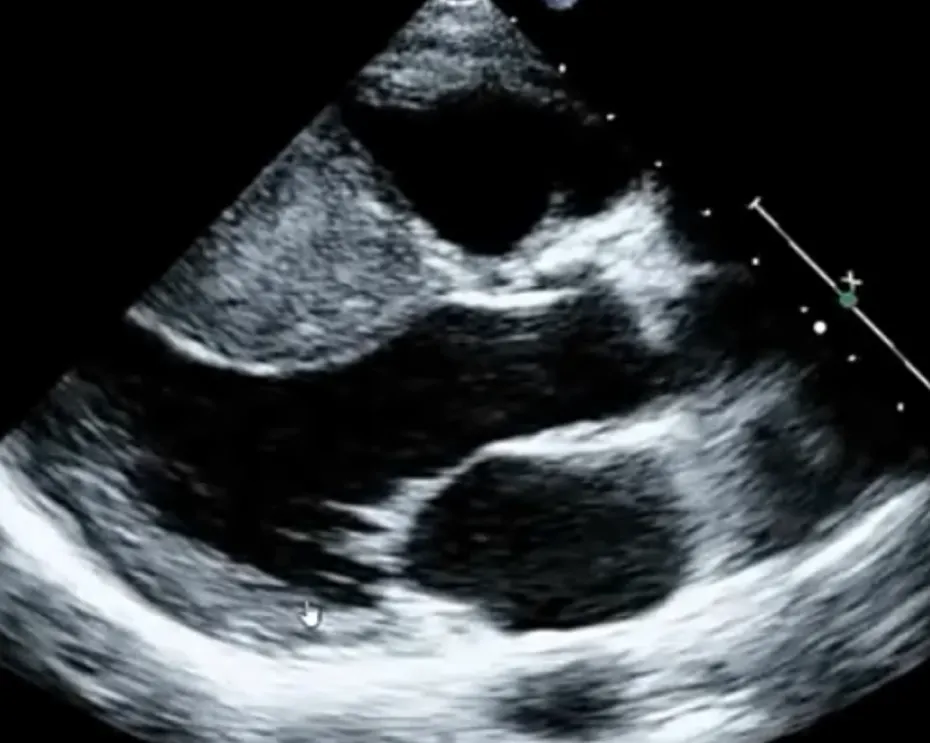

SAM in HCMP

Systolic anterior motion (SAM)

Narrow LVOT